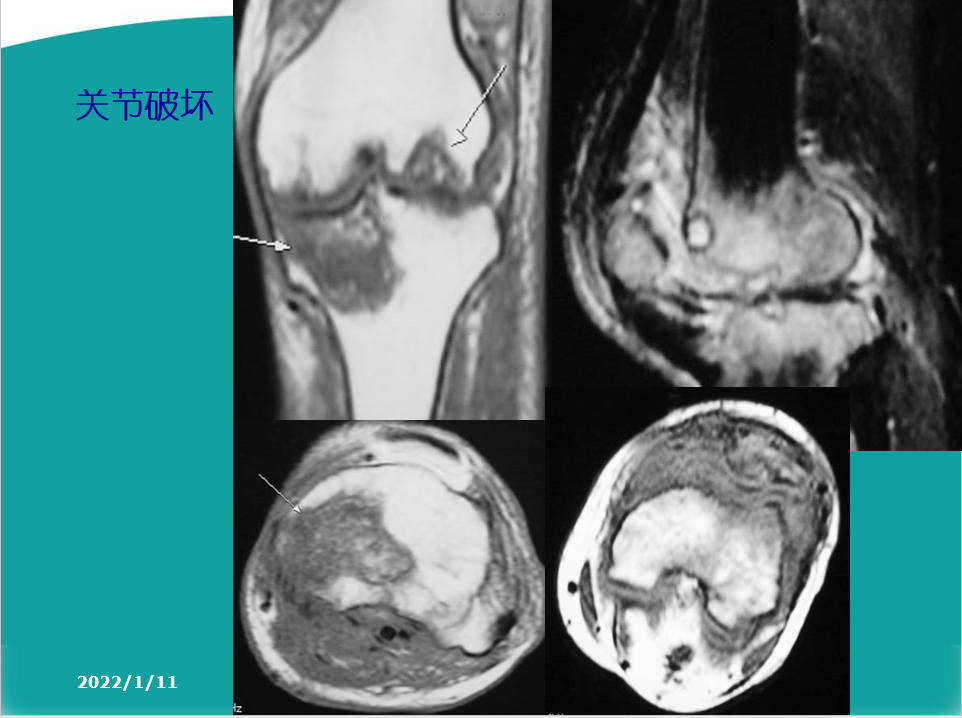

关节软骨的改变:软骨水肿、软骨囊性变、软骨变薄、磨损、软骨破坏